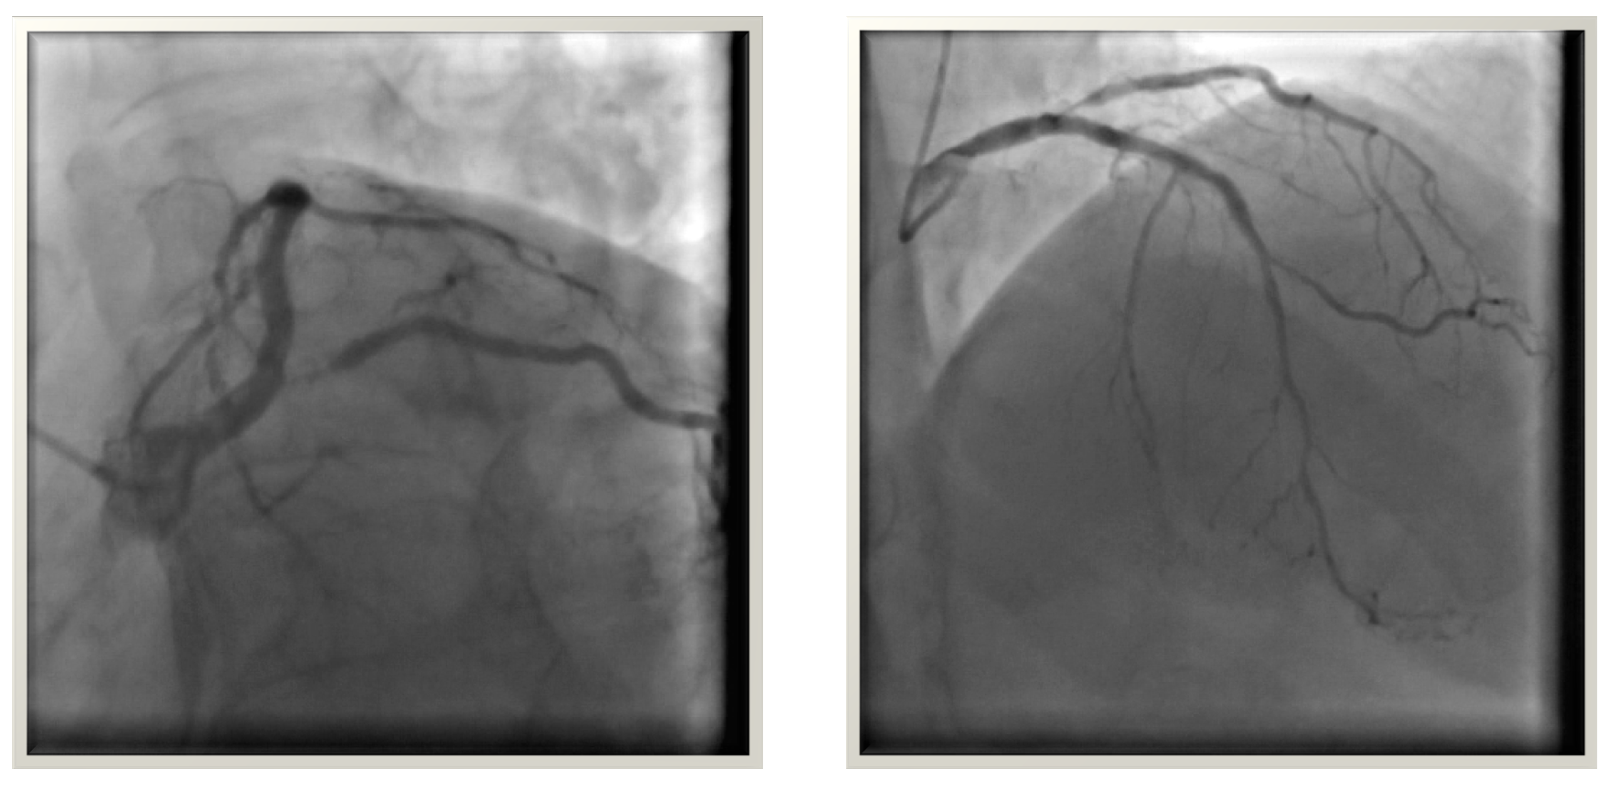

Coronary angiography revealed severe LCx ostial severe in-stent restenosis due to a crushed stent from proximal LAD stent protrusion into the LM. Patient developed contrast induced nephropathy after coronary angiography.

Challenges in this complex case included the risk of contrast-induced nephropathy, crossing the left main while avoiding floating struts of the LAD stent, and crossing to the LCx while avoiding the deformed LCx stent struts. IVUS-guided angioplasty was performed. Two guidewires were positioned intrastent: one in the LAD and one in the LCx through the protruding stent struts in the left main. After predilation of the LCx and POT on the left main under IVUS guidance, a drug-coated balloon was applied to the LCx. The procedure was finalized with a final POT on the left main. Final IVUS and angiography confirmed an excellent result. Total contrast used was 03 ml.

Case Summary